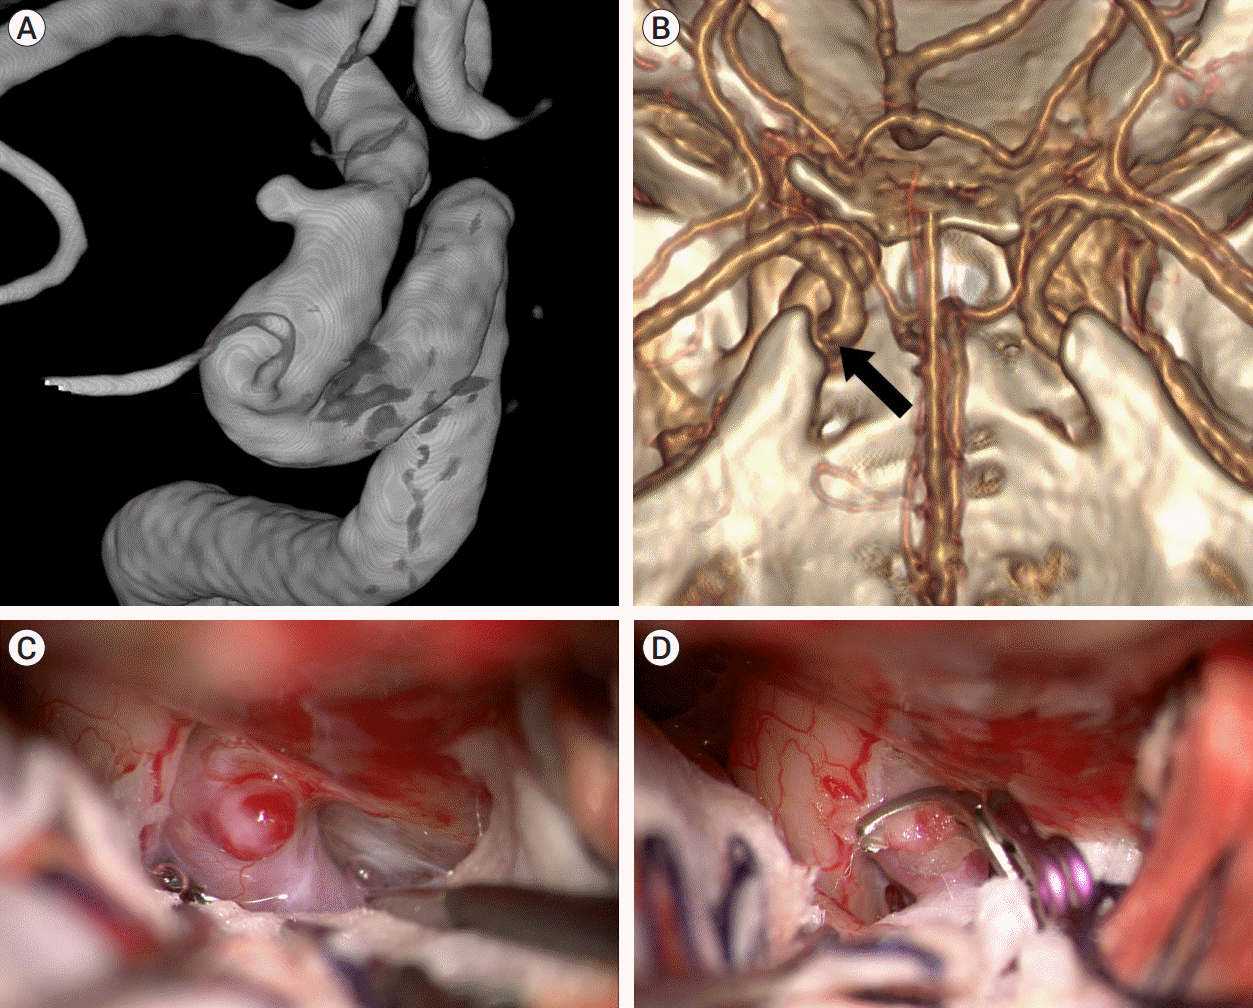

Fig. 3.

Case illustration 1: Aneurysm clipped without the need to cut the falciform ligament. (A) On the 25° rotated digital subtraction angiography image, a dorsal ICA aneurysm is observed distal to the ophthalmic artery. (B) 3D CTA with bone image revealed that the aneurysm (arrow) was situated distally to the ACP. (C) The aneurysm was not obscured by the falciform ligament. (D) The aneurysm was clipped without cutting the falciform ligament. ICA, internal carotid artery; CTA, computed tomography angiography; ACP, anterior clinoid process